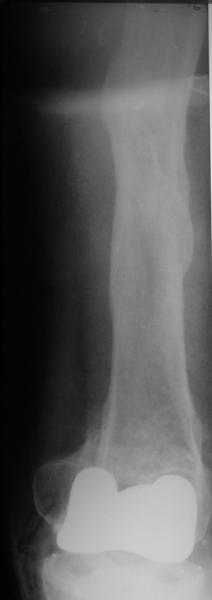

Видимо, самое "модное" на сегодня - малоинвазивный остеосинтез пластиной с угловой стабильностью. Распространенный вариант и закрытый интромедуллярный остеосинтез ретроградно. Хотя у нас было бы сделано антеградно - лешево и сердито, действительно малоинвазивно, в сустав не надо влезать. Нет риска прорезания порозной кости с миграцией в сустав, что возможно при ретроградном - гвоздь вводится через вырез в бедреннм компоненте, туда же может и вывалиться. А антеградный - упрется в протез. Как раз вчера заходил больной через полтора года после такой операции. Снимки в приложении.